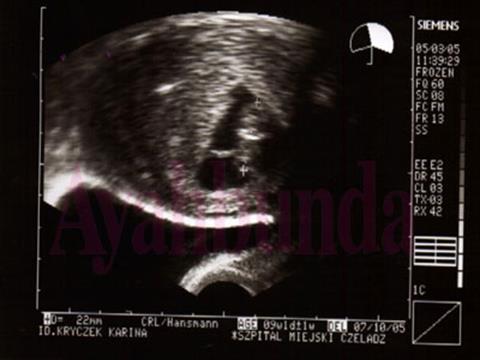

Pemeriksaan USG (ultrasonografi) kian hari kian populer di kalangan ibu hamil. Kalau dulu  dengan USG 2 dimensi (2 D), permukaan dan tekstur tubuh janin hanya berupa semburat warna hitam putih saja, sekarang sudah ada USG 3 dimensi (3 D) yang dapat memvisualisasikannya lebih jelas.

Apa sebenarnya pemeriksaan USG itu? Pemeriksaan USG ini  menggunakan gelombang suara  yang dilepaskan probe USG (alat yang ditempelkan ke perut pasien). Gelombang suara tersebut melewati jaringan tubuh, misalnya kulit, lapisan lemak perut, otot-otot perut, dan cairan ketuban, kemudian dipantulkan, ditangkap dan dimunculkan dalam bentuk gambar pada monitor. Gradasi kepekatan warna pada gambar tergantung materi apa yang dilewati dan memantulkanya.

Alat USG berkembang  dari waktu ke waktu. Awalnya, gambar yang  hanya berupa gambar 2 D (panjang x lebar).  Saat ini,  telah dapat pula gambar 3 dimensi dalam ukuran volume (panjang x lebar x  tinggi). Lebih  hebat lagi, gambar 3 D itu kini juga dapat dipancarkan dan ditangkap dengan kecepatan real time ibaratnya Anda menggunakan handycam. Itulah yang kita sebut USG 4 D.